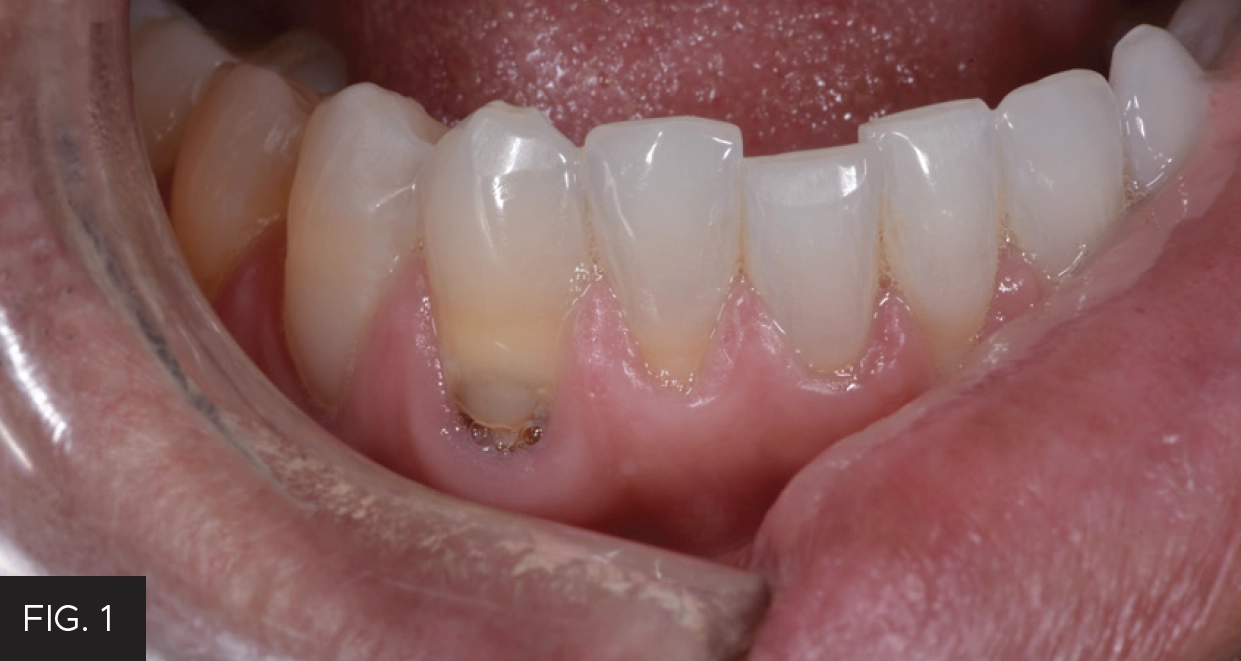

Following the laser tissue removal, a #0 retraction cord with ferric sulfate was placed to further hold the tissue in place and keep the area moisture-free. Although the tissue was isolated and retracted, there was some minimal bleeding present, which prevented a completely dry field. Retraction paste (3M™) was placed around both tooth preparations and completely covered the recently lasered tissue and cord. (FIG. 5) The retraction paste was allowed to set for 5 minutes. The paste was gently rinsed off to prevent rebound bleeding and the area was dried.